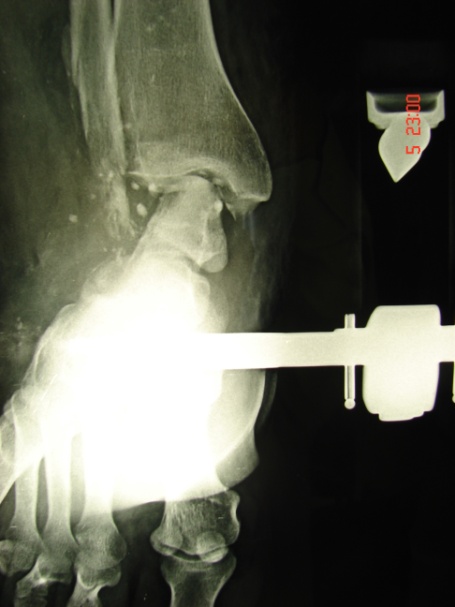

Εικόνα 4: α,β Προσθιοπισθία και πλαγία μετεγχειρητική ακτινογραφία της ποδοκνημικής άρθρωσης. Η αρθρόδεση έχει πραγματοποιηθεί με την τοποθέτηση ειδικού ήλου που συνδέει την πτέρνα, τον αστράγαλο και την κνήμη.

Μετά την αφαίρεση της εξωτερικής οστεοσυνθέσεως, λόγο της υφισταμένης αστάθειας στην υπολειπόμενη ποδοκνημική άρθρωση αποφασίστηκε να πραγματοποιηθεί αρθροδεση αυτής.